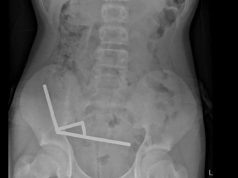

Denise Garcia, M.D., from the Medical University of South Carolina in Charleston, and colleagues conducted a retrospective study involving patients with a breast cancer diagnosis who presented for a second opinion to the NCI-designated cancer center at the Medical University of South Carolina. Reports generated after a multidisciplinary tumor board (MTB) review and subsequent workup were compared to radiology, pathology, and genetic testing results from outside institutions. Data were included for 70 patients seeking second opinions; 47.1 percent had additional radiological images.

The researchers found that 30 additional biopsies were performed in 25 patients; in 16 patients, new cancers were identified. Additional cancers were diagnosed in 22.8 percent of the 70 patients. A second opinion led to a change in pathology interpretation for 20 percent of the 70 patients. Eleven patients underwent genetic testing; none had a mutation other than a variant of unknown significance. As a result of the MTB review, 42.8 percent of the 70 patients had a change in diagnosis after a complete workup.